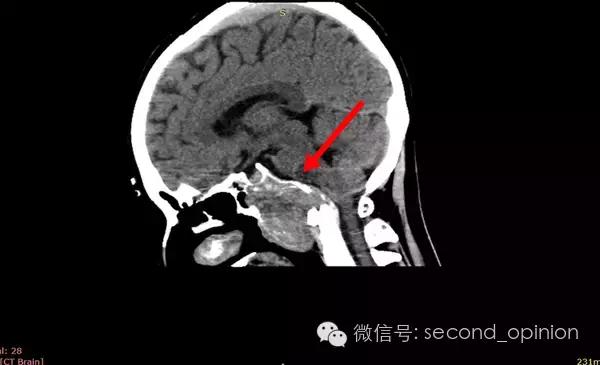

患者自2013年6月起无诱因出现吞咽困难,伴吐字不清症状,自觉舌肌无力一个星期,偶有头痛发作,不伴呛咳,呕吐,无抽搐发作。当时耳鼻喉科做相关检查,咽部无异常表现。行头部CT检查发现颅内占位,范围约43*30mm。保守治疗,后病情稳定,未发现症状明显加重。

至2014年1月,出现左耳耳鸣,表现为低调杂音,未发现听力明显下降,偶有脸部麻木,无面瘫。行MRI检查,颅内占位范围约60*45*47mm。2014年2月2日第一次手术,行内镜导航下经蝶窦颅底肿瘤切除术,切除体积约50*45*50mm,手术顺利,术后头痛症状消失。左耳低调耳鸣术后消失两周后再次出现,右耳术后出现偶发轻度耳鸣。2014年5月4日第二次手术,行内镜口鼻蝶入路脊索瘤切除术,切除肿瘤体积45*40*50mm,过程顺利,术后耳鸣消失,病情稳定后出院。

2014年6月15日 进行射波刀放疗,32.5Gy/5fx,剂量曲线69%包绕,治疗期间对症脱水,减轻放疗反应,完成全部治疗后出院。

2014年12月 进行质子放射治疗。

2014年9月1日MRI(手术治疗前)

质子治疗前